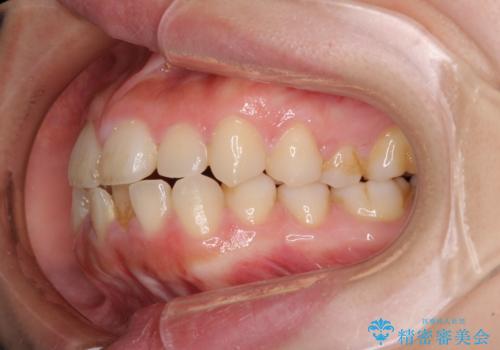

- 前歯が突出しているために口が閉じられないとのことで来院された患者様です。

上下ともに顎が小さく、歯列が前方に突き出していたため、上下左右の第一小臼歯4本を抜歯し、口元の突出感を改善していくこととしました。

口元の突出感が改善されると睡眠中の口呼吸が予防でき、鼻炎などの疾患予防に繋がると言われています。